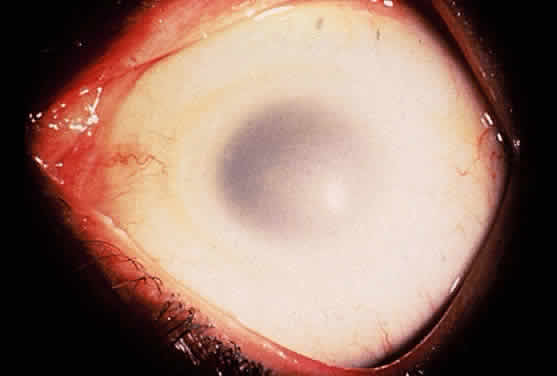

The lens in homocystinuria is much more mobile than in the Marfan syndrome. This may be related to the clinical observation of progressive irregularity of the zonular fibers and the appearance of a fringe of white zonular remnants at the equator of the lens and on the surface of the ciliary body (Fig. 1).12,13 Henkind and Ashton first reported histopathologically the ocular findings in four eyes of three homocystinuric patients. They found the zonular fibers to be deficient adjacent to the lens. These zonules had recoiled to the surface of the ciliary body and were matted and retracted into a feltwork that fused with a greatly thickened basement membrane of the nonpigmented epithelium. The greatly thickened basement membrane overlying the ciliary body in homocystinuria has subsequently been shown by electron microscopy to be composed of degenerate zonular material.14 In addition, Ramsey and coworkers noted that the degree of zonular abnormality was related to age: the younger the patient, the more normal-appearing zonular fragments composed of oriented filaments that could be identified.14 The zonular fibers are composed of glycoproteins with a high concentration of cysteine, which may explain their susceptibility to abnormal function in homocystinuria.15,16